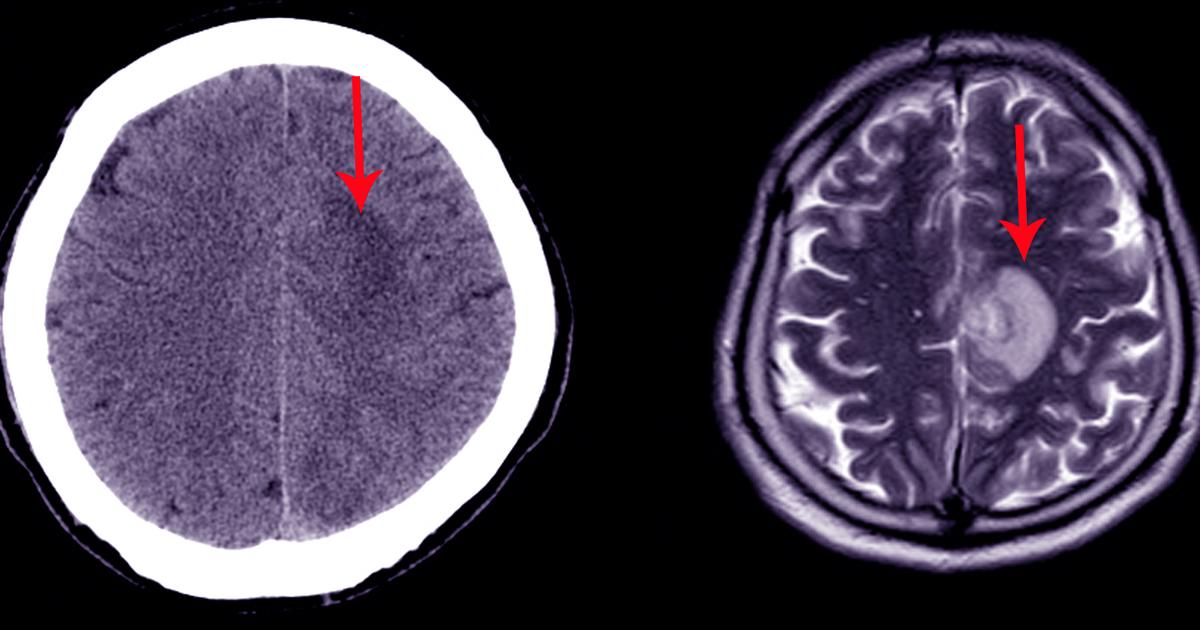

Serious Warning Signs Of A Cavernous MalformationA cavernous malformation is a type of rarely-occurring vascular malformation. Vascular malformations are abnormalities in how the blood vessels are formed.…November 1, 2019

Serious Symptoms Of A Subarachnoid HemorrhageA subarachnoid hemorrhage, a life-threatening type of stroke, occurs when there's bleeding in the brain. When this hemorrhage occurs, blood pools in the space…November 1, 2019

Guide To The Causes And Complications Of Pituitary TumorsA pituitary tumor is an abnormal growth of tissue in an individual's pituitary gland, the small region in the brain responsible for keeping the delicate balance in…October 31, 2019